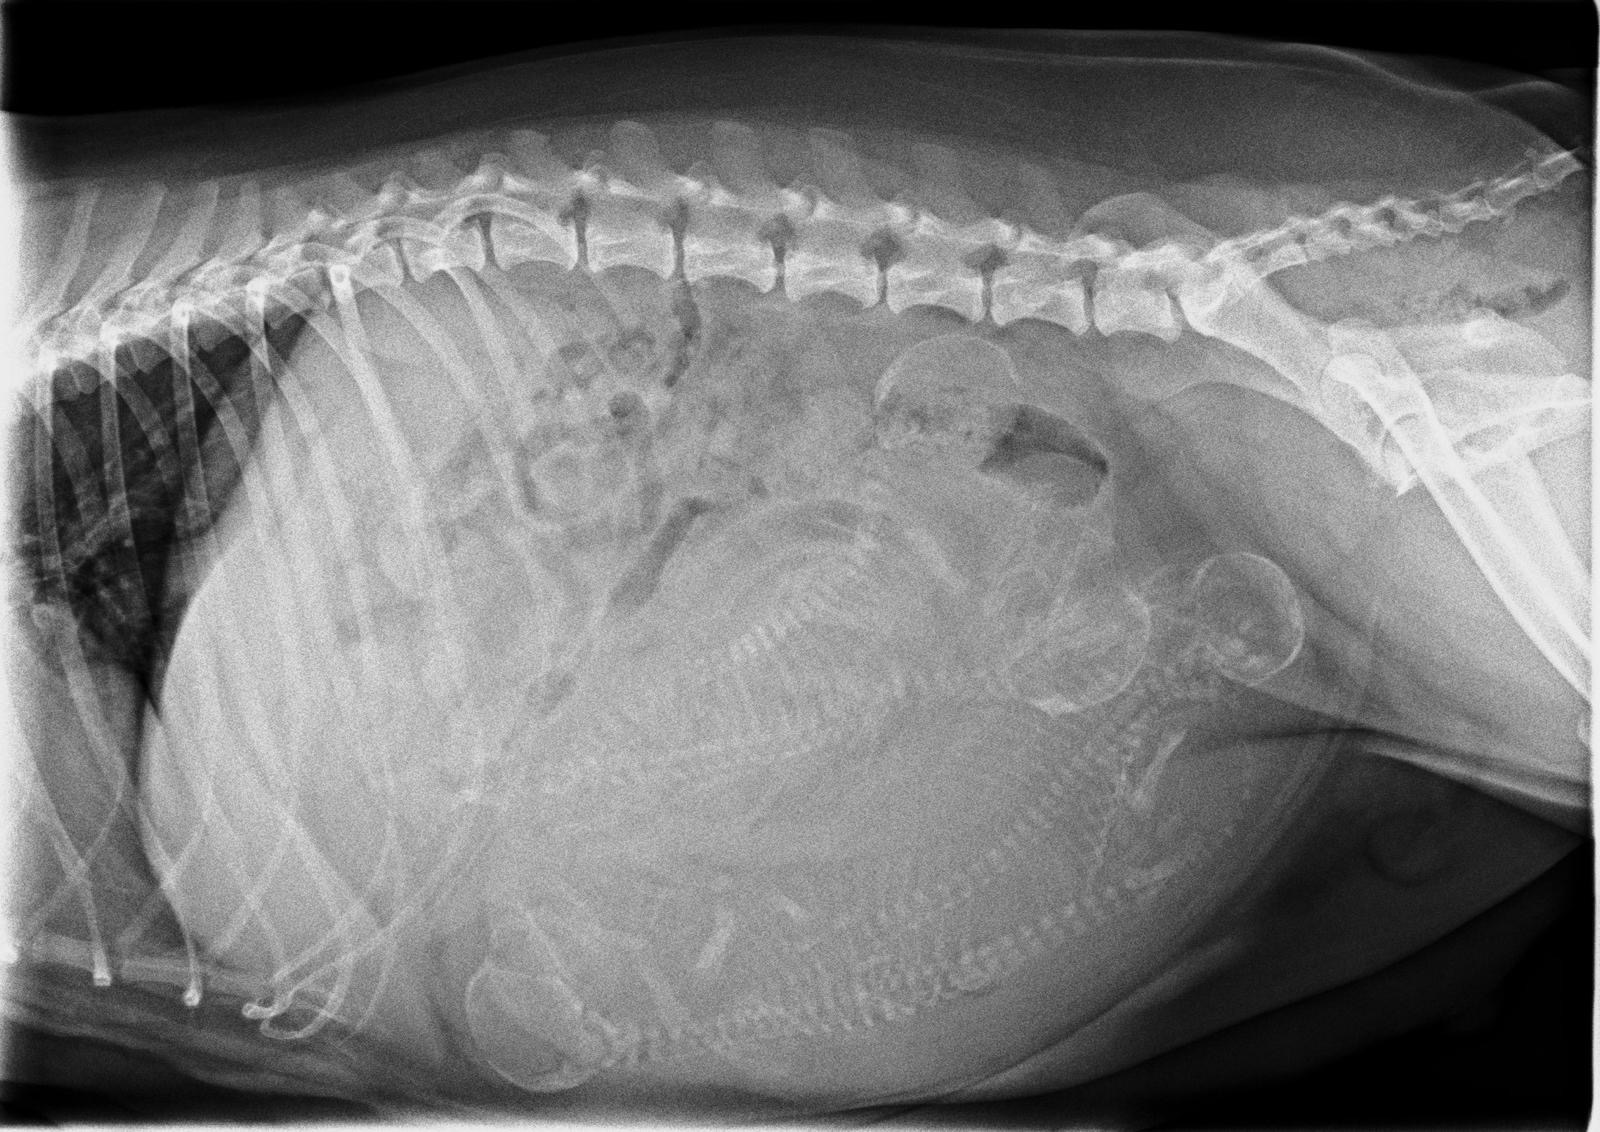

Röntgenbild Maite vom Nikolausberg: 4 Köpfe mit Wirbelsäule

Rund 1 Woche vor dem berechneten Wurftermin war unsere Maite vom Nikolausberg bei unserer Tierärztin Dr. Marianne Fischer zum Röntgen. Wir wollten ja wissen, mit wie vielen "Fellnasen" wir rechnen können, auch um bei der Geburt etwas mehr Sicherheit zu haben, dass alles problemlos abläuft. Deutlich zu sehen sind 4 kleine Vierbeiner. Maite's Gewicht und Bauchumfang nehmen fortlaufend zu und sie ist etwas ruhiger geworden, kann, wie immer, nicht genügend zu fressen bekommen.